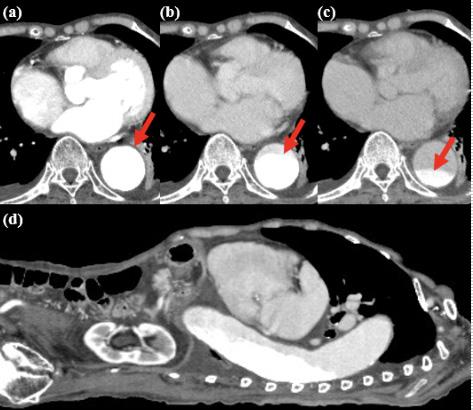

379 RUSH to the Diagnosis: Identifying Occult Pathology in Hypotensive Patients

10.SnyderAandSchmalzleSA.Spontaneous Streptococcuspyogenes pelvicinflammatorydisease;casereportandreviewoftheliterature. IDCases. 2020;20:e00785.

MiriamMartinez,MD,DrPH,MPH KhristopherFaiss,DO NehaSehgal,DO